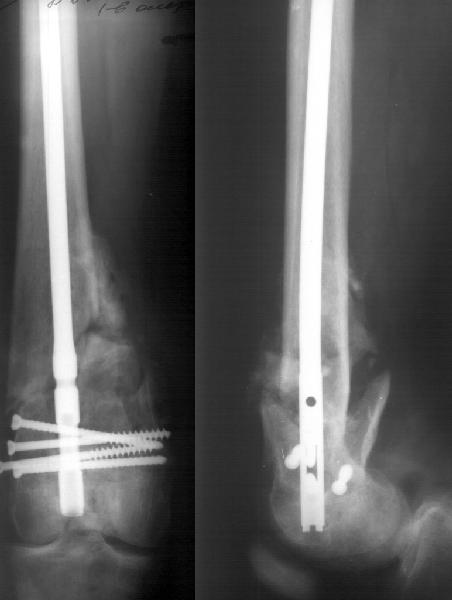

A mail 27 y.o. was operated Apr 2, 2002 2 weeks after injury (impact by a heavy construction) - he had open Gustilo II distal femoral fracture (image 1). Antegrade closed nailing by UFN 11 mm was performed (image 2). The second leg was amputated above the knee at the initial hosptial. To provide early weight bearing 6 mm locking screws were used so sll static holes were drilled accordingly. 2 months after the surgery he started to load the limb, before only knee ROM excersises were perfomed. The cyclic loadings produces stress riser and the nail was broken 10 days ago (image 3). Now he admitted to us again. It is the first case of such complication we meet. Now i plan to push the broken fragment distally and then perfrom retrograde nailing by UFN (distal femoral nails are not available in my settings). If the attempt would be too complicated we'll change to XF. Or plating is a good option here?